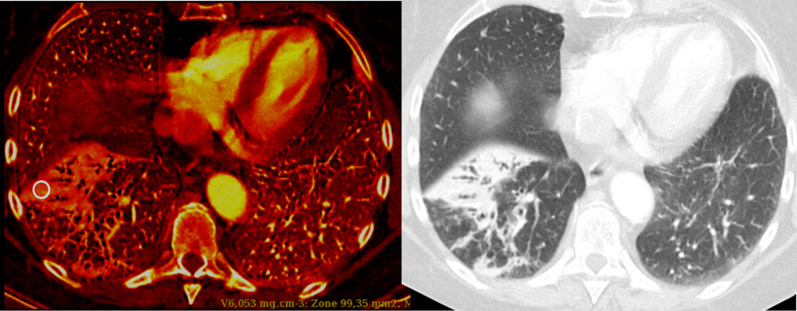

Fig. 4:

75-year-old female with bronchopneumonia and suspected PE. No perfusion defect was detected (PD-). Instead, a homogeneous high iodine distribution is seen (iodine map, left) matching consolidations in the right anterior basal segment (conventional lung images, right). The patient was treated with Ceftriaxone with a favorable outcome. Iodine concentration was measured at 6.053 mg/cm3 within the circle and at 0.723 mg/cm3 within the normal-appearing parenchyma